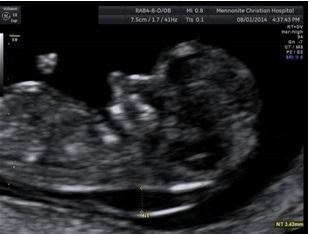

於早期的相關研究中,發現頸部透明帶的增厚與唐氏症,及其他許多染色體異常有高度相關,在後續的研究中,陸續加入的生化指標、以及靜脈導管逆流、三尖瓣逆流、以及鼻骨有無等等軟指標,讓系統的檢出率一路從80%左右提升到93%以上。而且,過程中的不斷發展,近年又加上了可以同時進行子癲前症的篩檢,以及早產評估 。當然,幾近99.5%以上準確率之非侵入性染色體篩檢(NIPS)的發展,則又是另一件事了(這題目請容後再談..)。

如果接受這項檢查,務必要搞清楚自己做的項目內容,以及所擁有的檢測率是很重要的,因為,這牽扯到您個人的風險管理。譬如說,有些院所只測量頸部透明帶加上抽血生化二指標。不做其他的軟指標,則檢測率只有80%,而不是加上靜脈導管逆流、三尖瓣逆流、以及鼻骨有無等等,全部標準量測的93%檢出率,這點,還是一定要搞清楚。

此外,因為畢竟這是源自超音波測量為基礎的檢查,所以再次強調,標準測量是非常重要的(因為很重要,請自己說三遍….),所以超音波儀器的解析度等級以及人員的專業訓練程度就非常重要了,但是很可惜的,目前台灣的醫療環境沒有辦法培養出那麼多的專業團隊。